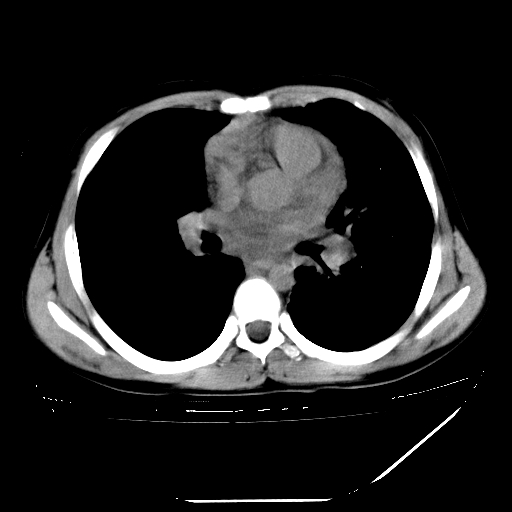

男,13岁,咳嗽、咳痰伴发热一周。

上纵隔课件多枚淋巴结,部分相互融合,左侧支气管壁增厚,肺纹理较右侧增粗,患者,男,13岁,

中上纵隔见多枚淋巴结肿大,部分相互融合成团片,左肺门增大,上叶支气管变窄,肺内多处斑片状 索条状及棉絮状致密影。临床“男,13岁,咳嗽、咳痰伴发热一周。”首先考虑:原发综合征!不除外淋巴瘤可能!

纵隔多发肿大淋巴结,部份有融合改变。双肺血管气管束增厚,以肺门为中心向外周散发,以左肺下叶为明显。考虑淋巴瘤可能性大。不除外原发综合征。

中上纵隔见多枚淋巴结肿大,部分相互融合成团片,左肺门增大,上叶支气管变窄,左肺支气管血管束增粗,可见磨玻璃样影。临床“男,13岁,咳嗽、咳痰伴发热一周。”首先考虑:淋巴瘤可能性大!